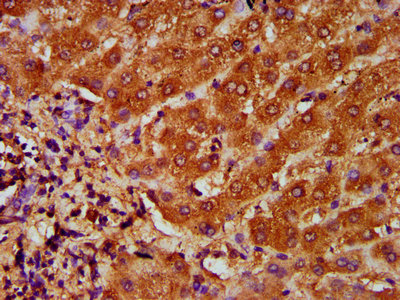

IHC image of CSB-PA14729A0Rb diluted at 1:200 and staining in paraffin-embedded human liver cancer performed on a Leica BondTM system. After dewaxing and hydration, antigen retrieval was mediated by high pressure in a citrate buffer (pH 6.0). Section was blocked with 10% normal goat serum 30min at RT. Then primary antibody (1% BSA) was incubated at 4°C overnight. The primary is detected by a biotinylated secondary antibody and visualized using an HRP conjugated SP system.